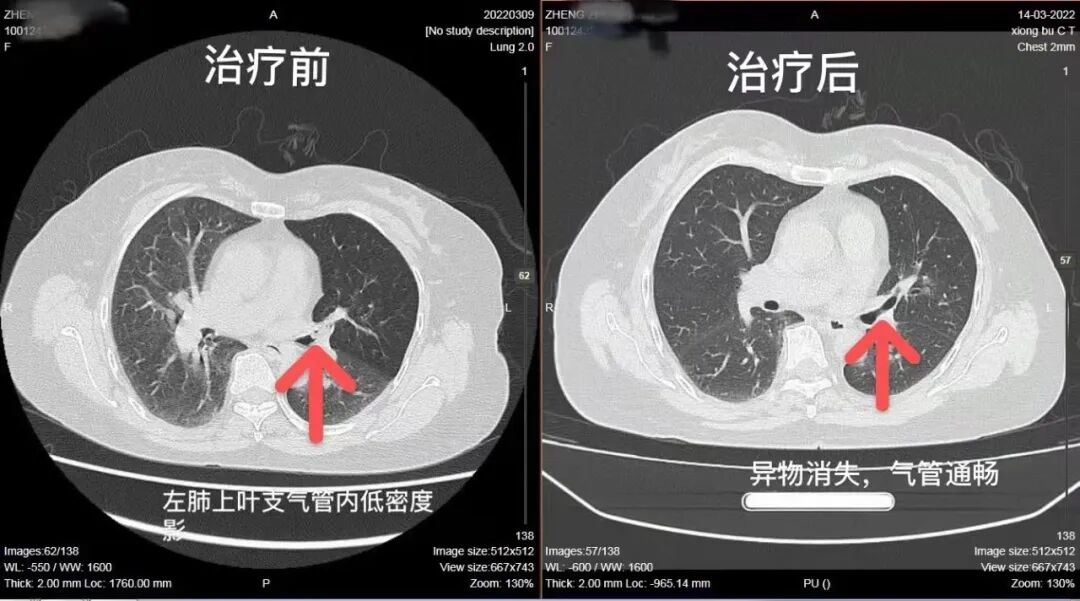

67岁的郑阿姨碰上这样一件“倒霉”事:吃花生米时,无意间呛入支气管,花生米“潜伏”1个多月,引发连续咳嗽、咳痰。幸好在珠海市第五人民医院呼吸与危重症医学科、麻醉科的合作下,郑阿姨的病症得到了治愈。1个多月以来,郑阿姨因反复咳嗽、咳痰,多次在附近诊所给予止咳、祛痰等治疗,虽然轮番进行口服药物、肌肉注射及静脉点滴等治疗,但症状完全无好转。近日,郑阿姨听朋友说珠海市第五人民医院呼吸与危重症医学科针对反复咳嗽病症,有完善的检查及治疗手段,立即来院就诊。接诊医生询问病史时,患者不经意的一句话引起了医生关注。患者自述1个多月前吃花生时出现呛咳,之后就开始出现咳嗽、咳痰。无论白天黑夜,咳嗽均较明显,并有进行性的加重。经胸部CT检查,结合患者病史,呼吸与危重症医学科姬路鹏副主任医师排除其他原因,明确为支气管异物。鉴于医院已开展无痛支气管镜检查及治疗,在麻醉科李先花主任的配合下,姬路鹏副主任医师决定为患者实施支气管镜下异物钳出术+喉罩插管静脉复合全麻术。

姬路鹏副主任医师介绍,与常规支气管镜检查相比,在全身麻醉的同时进行镜下检查及治疗,能够极大降低患者的痛苦,还能明显减轻支气管镜镜身及镜头引起的气管周围粘膜擦伤。同时,喉罩置入方便,无需暴露声门,还不占用气管空间,可以为纤维支气管镜操作和通气提供更大空间,解决术者和麻醉科医生共用气道的问题,从而减少不良反应的发生。在为患者治疗的过程中,发现由于异物呛入气管的时间过长,异物已完全卡死在左肺上叶固有支开口处。异物周围粘膜肿胀,肉芽组织增生,强行取出必定会损伤粘膜,甚至可能造成大量出血。

姬路鹏副主任医师考虑异物质地较脆,可以尝试破坏异物整体结构,分多次、小部分进行钳取。在调整为活检钳进行多次钳夹出数块碎物后,异物体积较最初缩小近一半,牢固性也随之下降,换为异物钳后一次性顺利取出异物。

此次手术用时近2小时,患者各级气管通畅,无异物残留,未见粘膜损伤。患者在麻醉苏醒后自述,呼吸顺畅,咳嗽减轻。